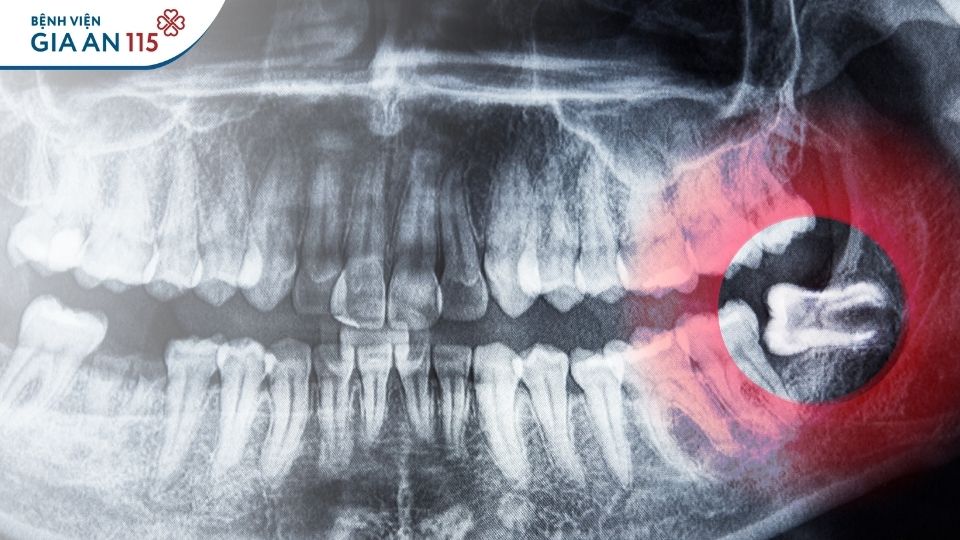

Răng khôn mọc lệch dễ gây các vấn đề răng miệng

Răng khôn mọc lệch gây đau, nhiễm trùng cần được nhổ bỏ (Ảnh minh họa internet)

Nhổ răng khôn được BHYT chi trả khi có bệnh lý kèm theo (Ảnh minh họa internet)

- Để xác định vị trí răng và hướng mọc răng, bác sĩ sẽ chỉ định chụp X-quang. Sau khi có kết quả, bác sĩ sẽ đưa ra hướng xử lý phù hợp giúp việc nhổ răng diễn ra an toàn tuyệt đối.